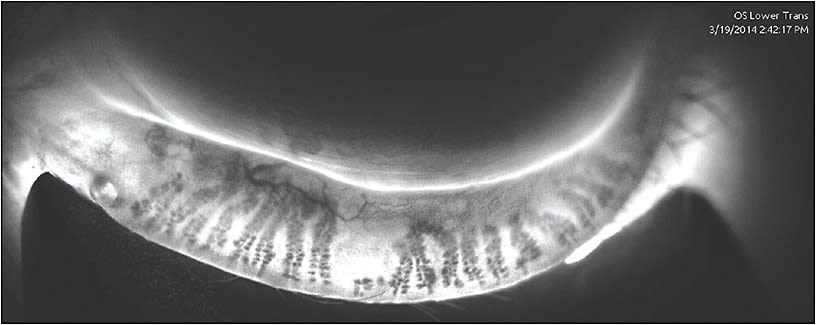

In addition, the routine use of LipiScan has been a fundamental change in our practice. We automatically scan every patient, looking for gland atrophy and structural changes to the meibomian glands, rather than waiting for patients to report symptoms. I can predict potential problems for patients with LipiScan and it is a great educational tool.

During my clinical examination, I first look at the lid margins to determine if disease is present. Then, I move on to the meibomian glands and examine the quality of the meibum that I express. Combined with LipiScan, this is a simple and efficient way to evaluate every patient.

When using the LipiScan with Dynamic Meibomian Imaging, I can evaluate the anatomy. If a patient has lost 50% of his meibomian glands, I tell him, “We need to maintain the remaining 50% for the rest of your life to avoid discomfort, poor vision, and potentially significant pathology.”

Dr. Epstein: I see many patients on referral, and I tend to spend more time with them because their disease is usually advanced. To me, meibography is worth its weight in gold. I have become quite the aficionado in using this technology and can explain it to patients. I think it really reinforces that they can be helped because they have a problem that is visible and discernible, and that they can understand. Point-of-care testing is certainly helpful. If I had to choose only one, it would definitely be LipiScan.